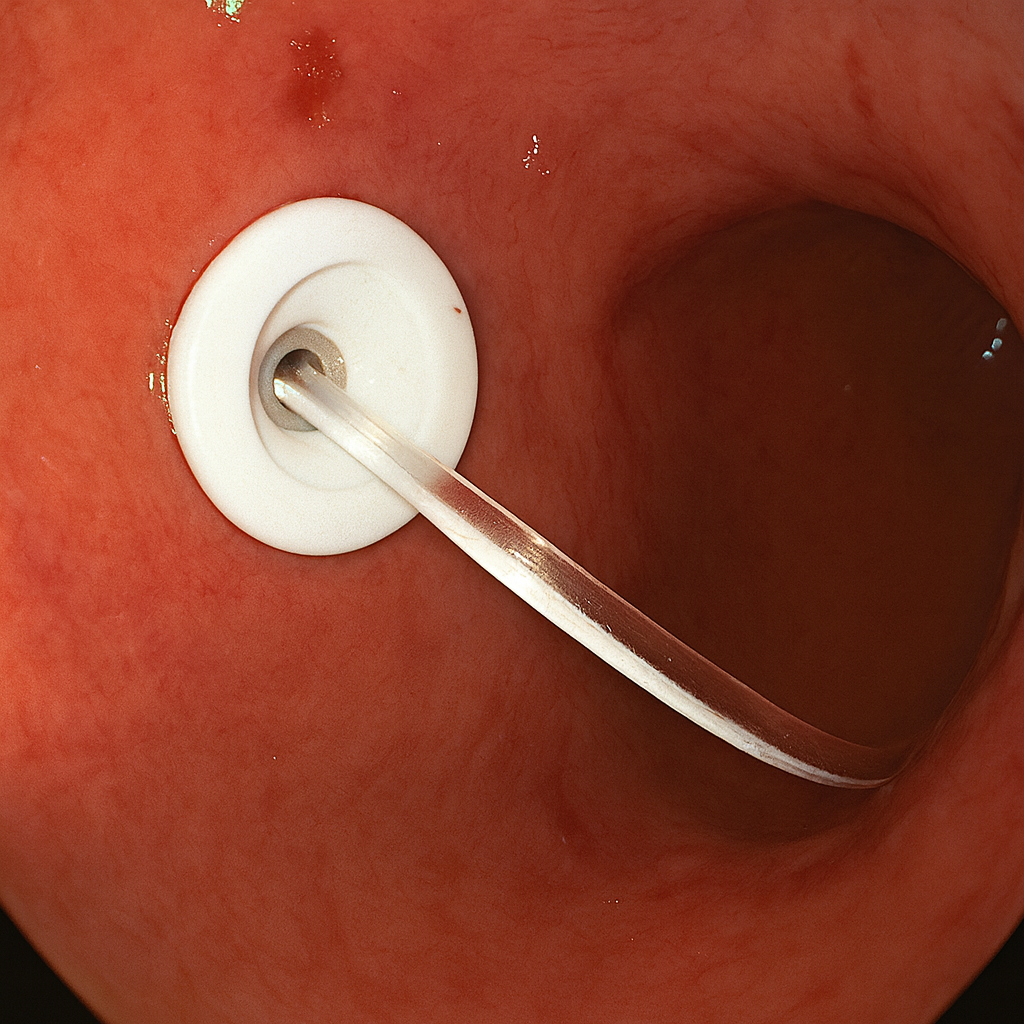

El Dr. J. Víctor Gómez es un especialista con amplia experiencia en endoscopía gastrointestinal, que realiza procedimientos avanzados como la gastrostomía con colocación simultánea de vías hacia el estómago y el intestino en una misma sonda, ofreciendo a sus pacientes alternativas seguras y efectivas para su nutrición y cuidado integral.

- GASTROSTOMÍA ENDOSCÓPICA PERCUTÁNEA

- Procedimiento endoscópico de mínima invasión

- Evita cirugía

- Se coloca sonda directamente al estómago

- Permite nutrición y administración de medicamentos

- Alternativa ante la dificultad para deglutir

- Manejo sencillo en casa

- SONDA DE EXTENSIÓN ENTERAL

- Se coloca a través de la sonda de gastrostomía

- Sonda de alimentación enteral continua

- Disminuye el riesgo de reflujo y broncoaspiración

- Permite dar alimento simultáneo mientras se dan medicamentos

- Permite mejorar la nutrición

- Ofrece dos vías digestivas simultáneas